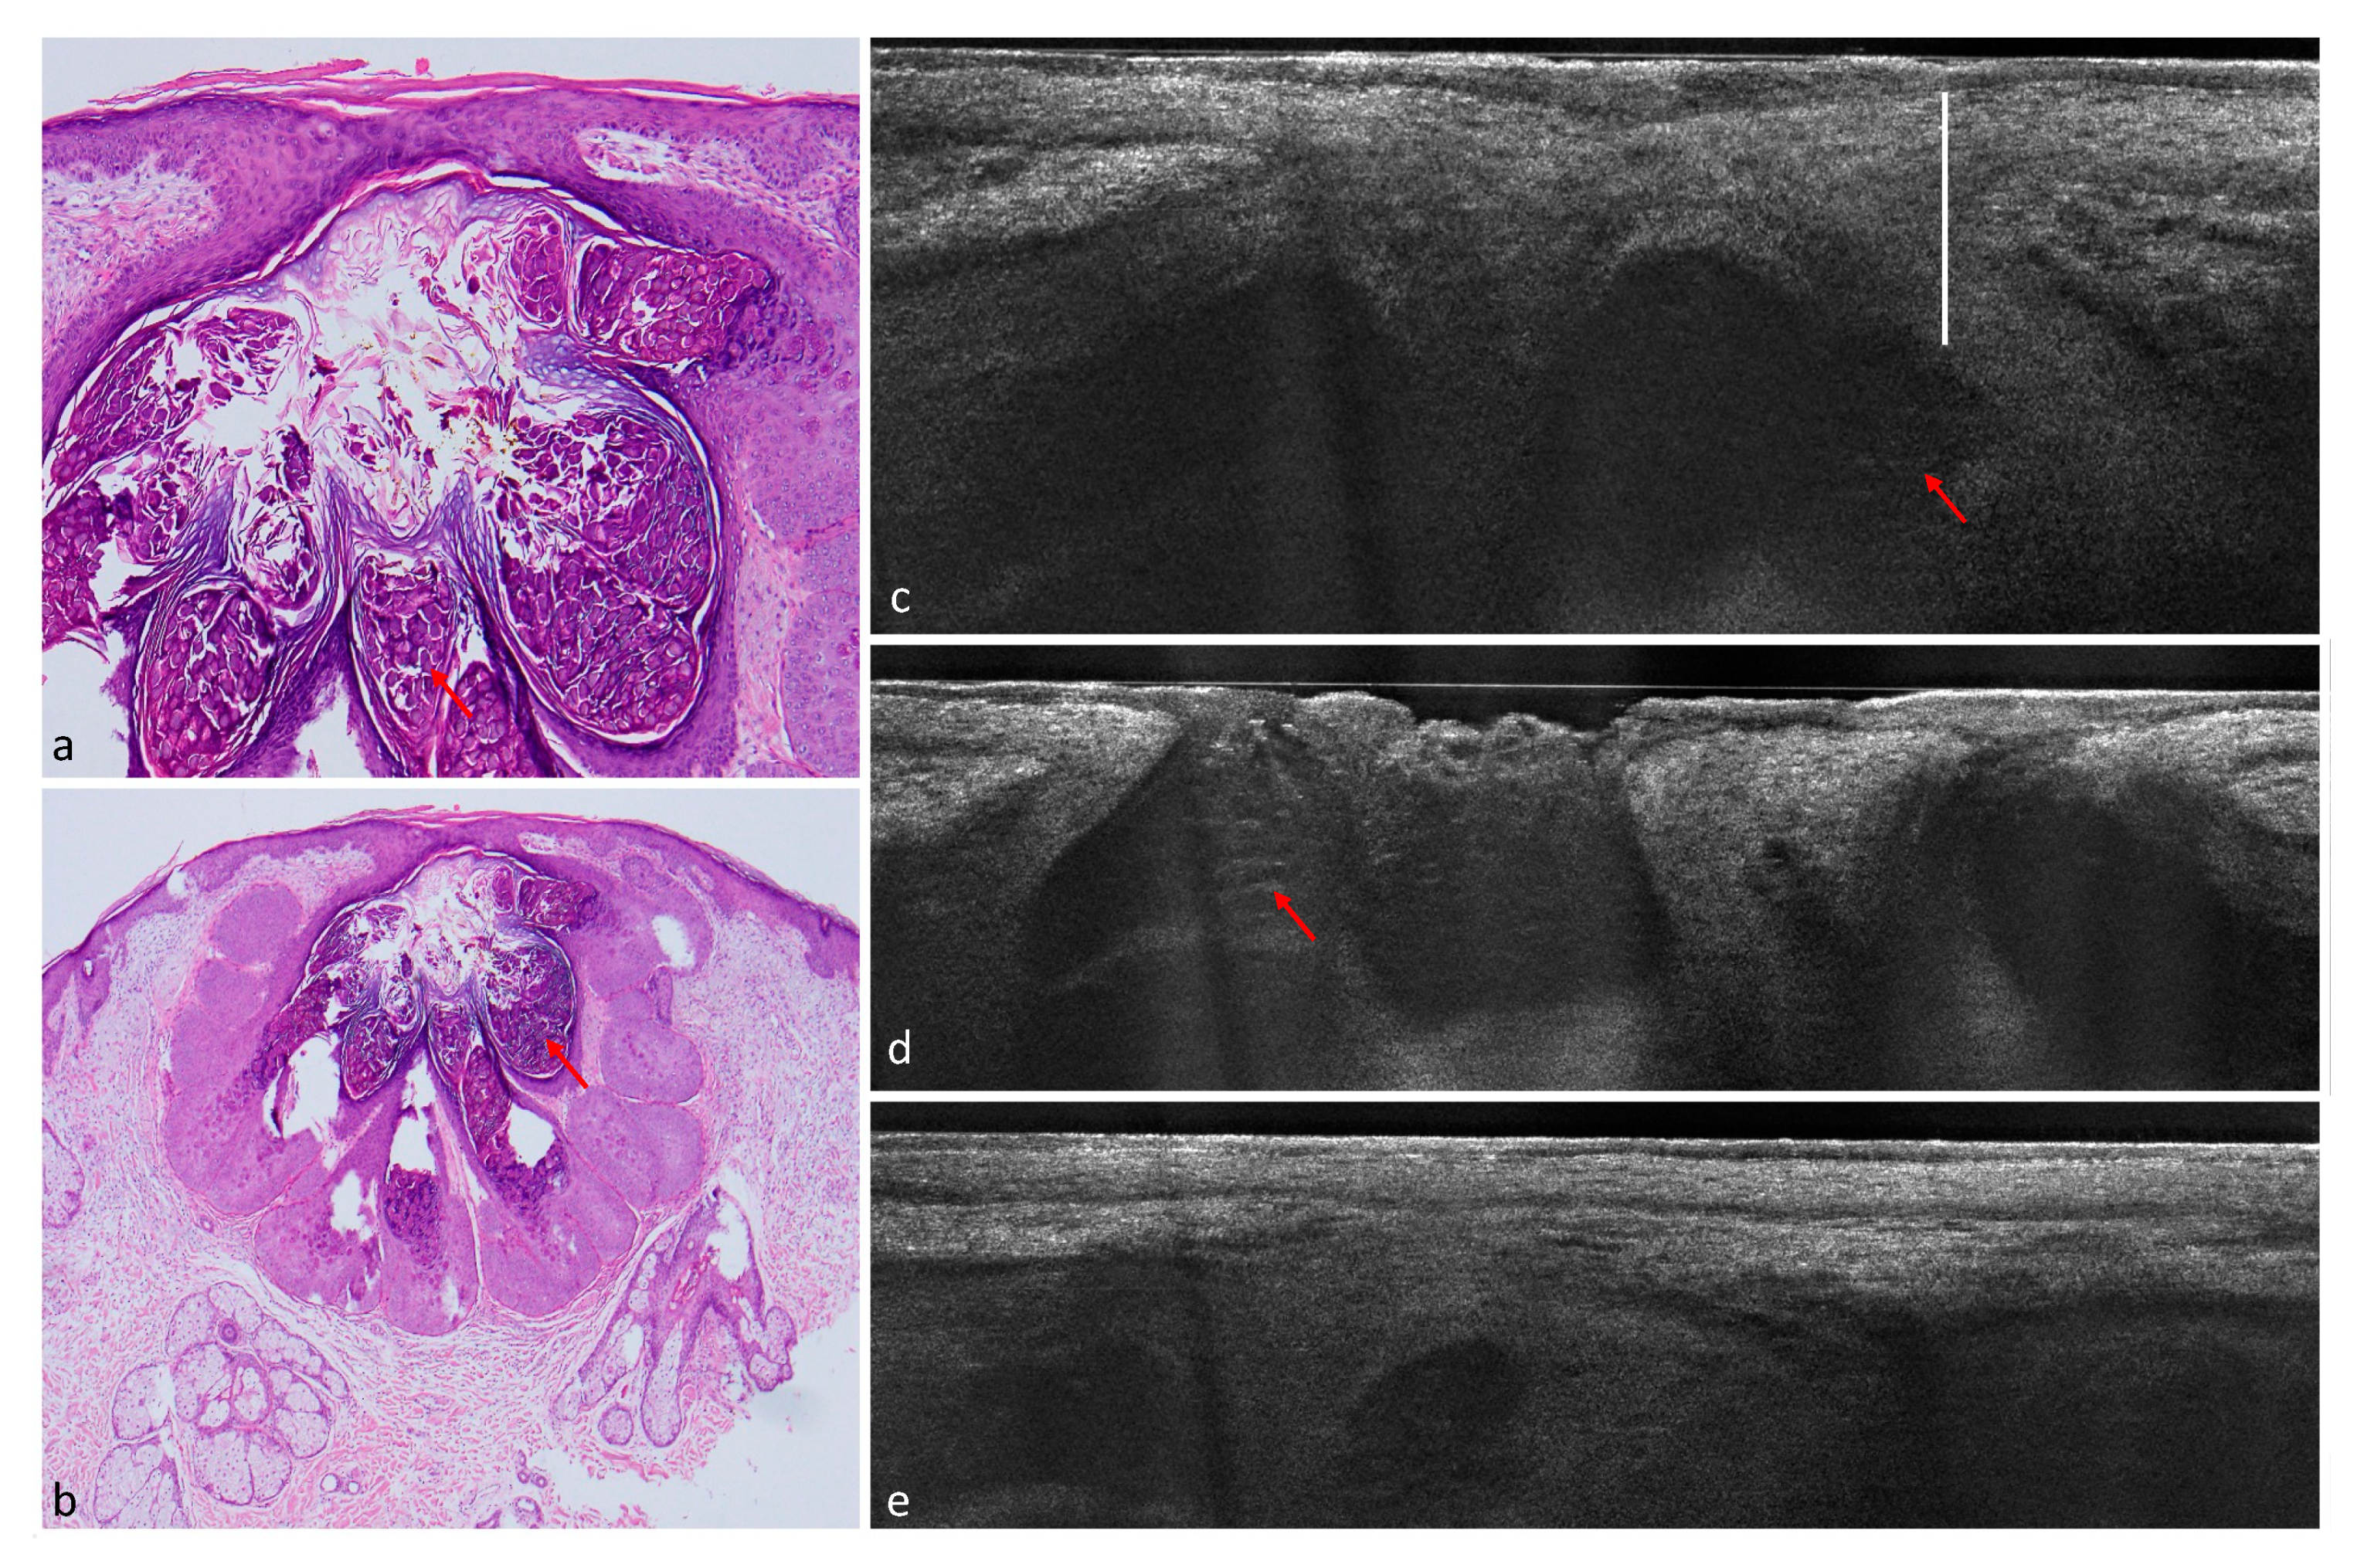

Figure 2. Nodular BCC with cystic parts in the nasolabial fold of a 76-year-old patient. (a) (200×) and (b) (100×): histological HE-stained sections. Peritumoral clefting (white arrows) and cystic structures (asterisk). (c) LC-OCT image of the same lesion. Arrows again indicate clefting, the BCC has a fine granular texture. (d) dark hyporeflective area (asterisk) in a cystic BCC corresponding to glomerular vessels.